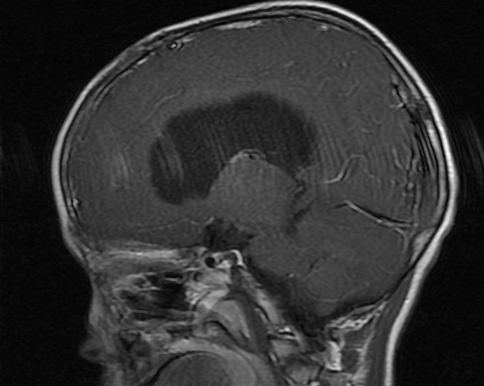

经日本国立癌症研究中心东医院质子治疗后,患儿于2021年05月12日在中国进行第1次复查:

颅脑MRI检查

图8

图9

我已经确认了该患儿的影像。

与2021年1月治疗前的MRI影像相比较,病灶没有大的变化,并且没有增大倾向。因为治疗结束后刚刚2个月,所以请继续定期复查MRI检查。